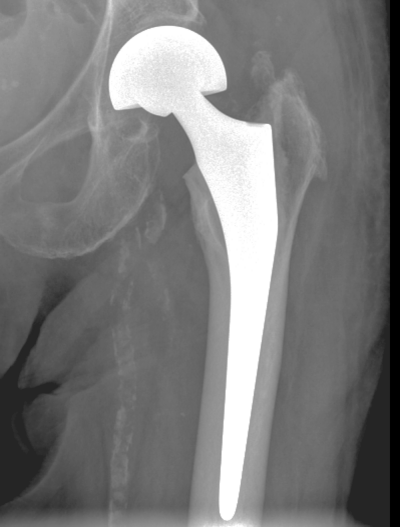

Hüftgelenksnahe Oberschenkelbrüche

Hüftgelenksnahe Oberschenkelbrüche bezeichnen die knöchernen Verletzungen des Hüftkopfes, des Schenkelhalses oder des Rollhügelmassivs (Trochanter major und minor). In der Regel ist ein Sturz auf das Hüftgelenk oder ein direktes Anpralltrauma dafür verantwortlich. Diese Frakturen sind typische Frakturen des höheren Lebensalters.

Die Patienten werden fast ausnahmslos über die Rettungsstelle in unsere Klinik eingewiesen. Klassische Symptome sind die Gehunfähigkeit, starke Schmerzen und ein nach außen verdrehtes Bein. Lokale Blutergüsse sind häufig vorhanden.

Modernste radiologische Diagnostik steht uns zur Klassifizierung der Fraktur und der sich daraus ergebenden Therapie zur Verfügung.

Patienten-individuelle Faktoren wie Allgemeinzustand, Vorerkrankungen, Begleitverletzungen, ein vorbestehender Hüftgelenksverschleiß fließen mit in die Therapieplanung ein und werden mit den Patienten besprochen. Die operativen Behandlungskonzepte unserer Klinik für diese Verletzungen entsprechen den aktuellen Leitlinien bzw. den internationalen Therapie-Empfehlungen.

Die operative Therapie erfolgt zeitnah zum Unfallgeschehen, kann sich aber durch einen reduzierten Allgemeinzustand, erhebliche Nebenerkrankungen und insbesondere durch die Einnahme von blutverdünnenden Medikamenten verzögern.